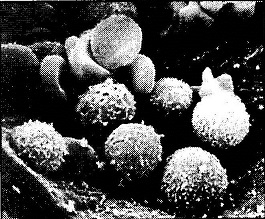

खून का संगठनः इंसानी खून में लाल एवं श्वेत रक्त कणिकाओं के अलावा प्लेटलेट्स, लवण, अमीनो अम्न वगैरह भी मौजूद होते हैं। रक्त कोशिकाओं का माइक्रोस्कोप से लिया गया फोटोग्राफ - जिसमें लड्डू की आकृति वाली श्वेत रक्त कणिकाएं और चपटी गोलाकार लाल रक्त कणिकाएं दिखाई दे रही हैं। आम तौर पर लाल कणिकाओं का व्यास लगभग 8 माइक्रोमीटर व मोटाई 2 माइक्रोमीटर होती है. श्वेत रक्त कणिकाओं का व्यास 8-15 माइक्रोमीटर और प्लेटलेट्स का साइज़ लगभग 2-3 माइक्रोमीटर होता है।

खः लिम्फ गठान के एक हिस्से का इलेक्ट्रॉन माइक्रोग्राफ (100x)